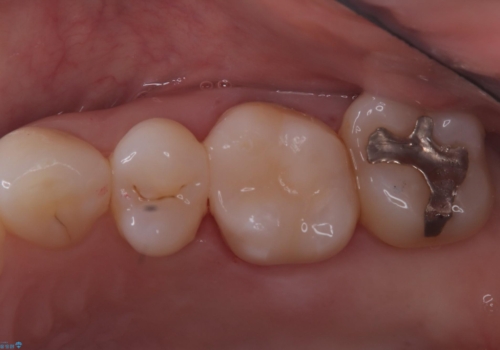

適合性・審美性を考慮し、セラミックインレーでのやり替えとなりました。